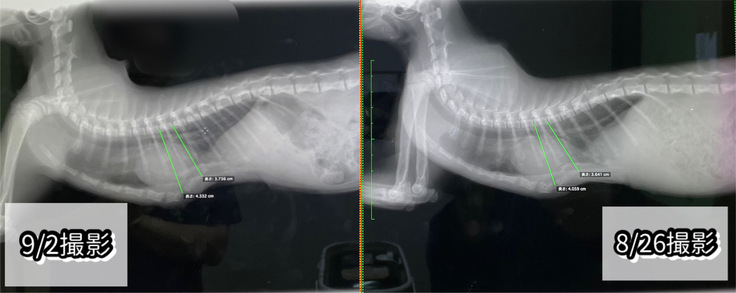

9/2(土)術後9回目の診察

本日はレントゲンと傷口の消毒(抗生物質の注射)、

2回目の混合ワクチンをしてきました。

レントゲンは身体が大きくなってきたからか、

胸骨は先週よりも3〜4mmほど広がっていました。

が、肋骨の先端?あたりの骨が先週よりも戻ってしまっていて、

再手術するまでではないけれど、

『軽度の漏斗胸』ぐらいには今後なってしまうかも…、と。